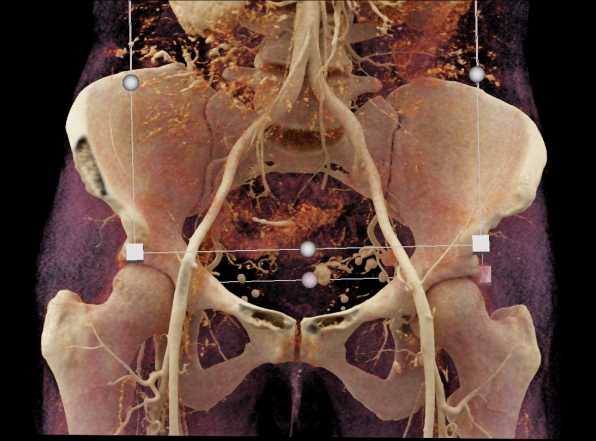

Urachal Carcinoma of the Bladder